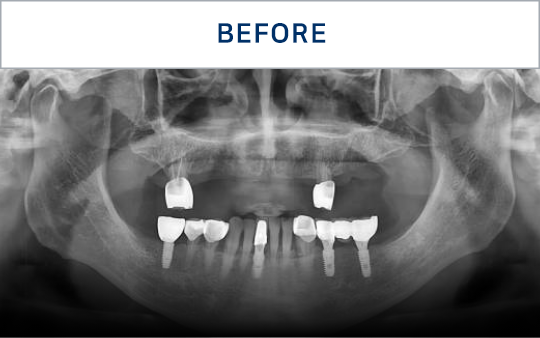

전후가 명확한 결과, 그 결과가

곧 신길플란트치과의 신뢰입니다.